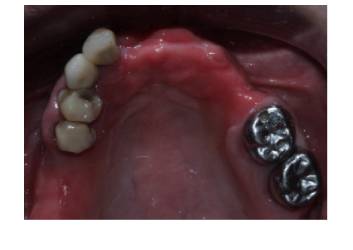

• The upper arch was restored using a digitally milled titanium iBAR framework. It was topped with Illusion Zirconia Dental Bridge. This provided them with an extremely precise fit and long-term stability. (Fig: 3.1, 3.2)

Occlusal view of maxillary implant fixtures (Fig 3.1) and the completed iBAR-supported Illusion Zirconia prosthesis (Fig 3.2).